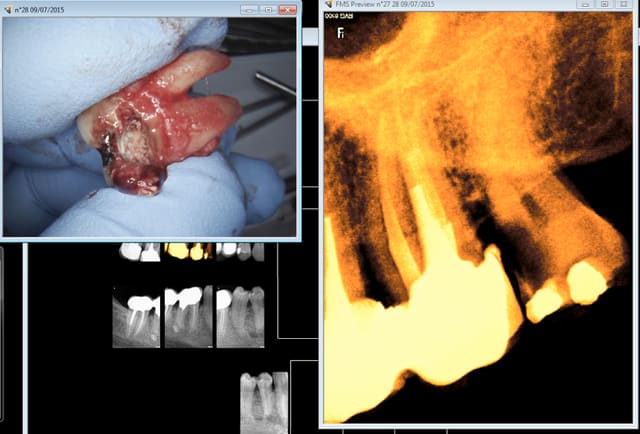

C'est moi qui l'ai extraite celle là justifié et prouvé pas pour le plaisir. mais bon qui viendrait me les gonfler pour 33 euros ? -))))